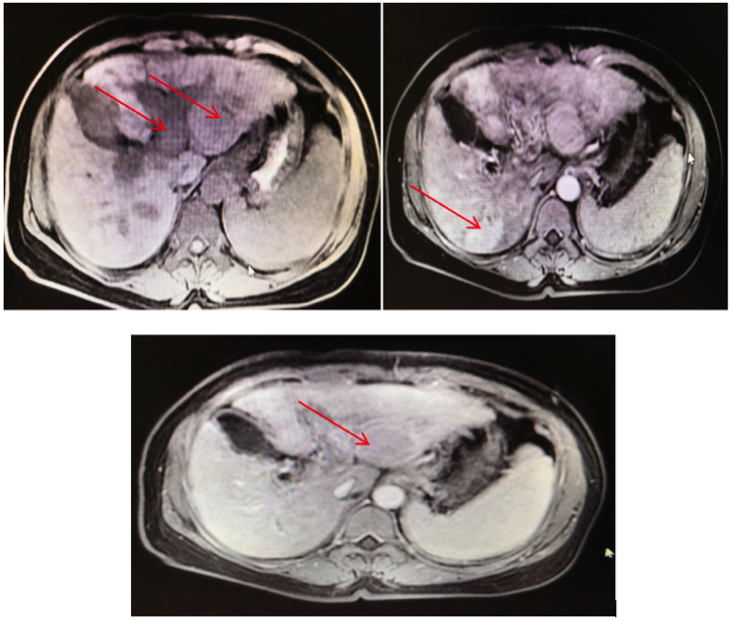

2019年10月8日复查腹部MRI,提示肝内病灶较前明显缩小,临床评价为疾病稳定(SD),见图2。

2019年12月2日复查腹部MRI肝内病灶进一步缩小,疗效评价为PR(图2)。2.png

图2. 患者接受仑伐替尼联合信迪利单抗治疗后肝内病灶持续缩小